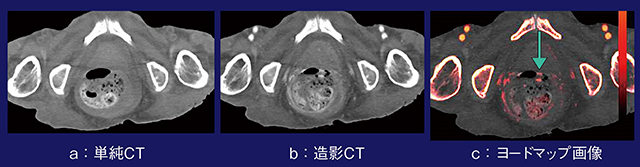

症例3は,82歳,男性,急性腹症である。単純CTと造影CTだけでも腸管が絞扼しているのが確認できるが,腸管壁の造影効果が不明瞭で,正常な壁との違いがわかりづらい(図3 a〜d)。造影CTのヨードマップ画像では腸管壁の造影効果が明瞭で,虚血状態を判別しやすい。もともと腸管出血などで腸管壁が高吸収として描出される状況においても,造影効果との判別ができ有用である(図3 e,f)。本症例は,手術にて腸管壊死を来していたことが確認された。

図3 症例3:ヨードマップ画像による絞扼性腸閉塞の虚血の評価

症例5は,70歳,男性,下血のある症例である。造影CTでは便も白く描出されるため(図5 b),造影剤との判別が困難であるが,ヨードマップ画像では濃染が確認できる(図5 c)。ヨードマップ画像は,ヨード以外にも高吸収なものは淡く描出されることがあるため注意して読影する必要があるが,腸管内の血管以外の構造物が区別可能であり,今後の応用が期待できる。

図5 症例5:ヨードマップ画像による腸管内の便と造影剤の鑑別